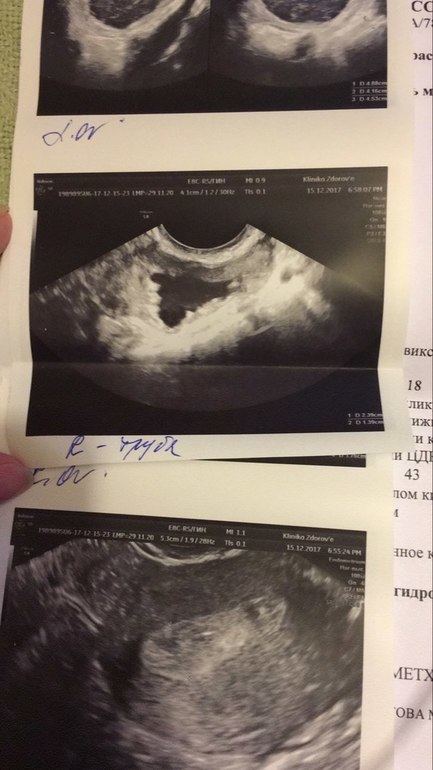

Смотрим через 2 недели - все то же подозрение. РЕ назначает идти к экспертному специалисту с хорошим аппаратом, которая без сомнения ставит диагноз "Правосторонний гидросальпингс". (Добавлю примечание - РЕ рекомендовала как к специалисту из своей клиники, так и к "стороннему специалисту").

ПС Лапару планирую делать по ОМС , буду просить направление в жк. Связалась уже с врачом, которая делала ГСГ и удаляла полип. Говорит, бери заключение, чтобы было написано "удаление".- Это они так перестраховываются? А вдруг там не гидрос, все равно резать будут? Имею ли я право получить заключение чтобы там было написано что-то типо " Удаление только по показаниям, т.е по ситуации" Девочки подскажите пожалуйста 😓 Картинку прилагаю: